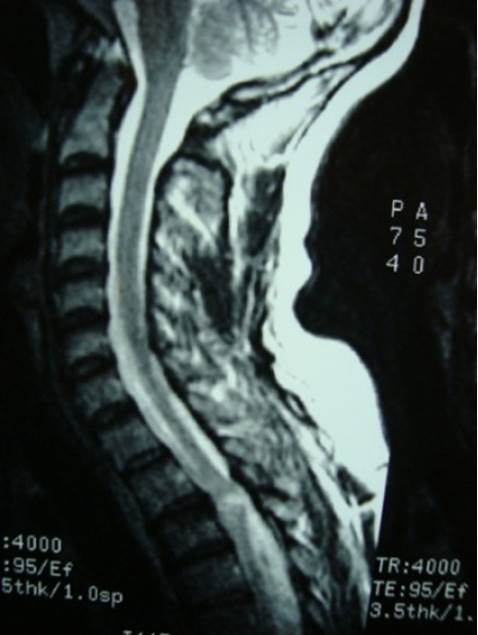

Se le realizó TC de tórax y raquis torácico que evidenció una fractura de la lámina de T3 izquierda (Figura 1) y se completó la valoración con una IRM de raquis dorsal (Figura 2) que evidenció una alteración de la señal hemimedular izquierda a nivel T2-T3. Se opto por tratamiento conservador haciendo cierre simple de la herida dorsal.

A nivel dorsal donde las láminas suelen estar sobre-montadas es más frecuente que se asocie una fractura con desplazamiento de fragmentos óseos hacia el canal asociada a lesión medular (como sucedió en el tercer caso) 9). En estos casos la lesión sería por contusión medular y no por laceración directa por el objeto penetrante.

La contusión o edema medular también se visualiza como una imagen hiperintensa en T2 e hipointensa en T1 6,19,26,29). En nuestros casos 2 y 3 se evidenció una contusión medular que en el segundo caso comprometía toda la extensión transversal de la medular y en el tercer caso sólo una hemimédula. Puede no verse ninguna alteración de la señal medular en la IRM a pesar de que haya déficit neurológico sin que esto invalide el diagnóstico 18,29, como sucedió en nuestro primer caso. El aire intrarraquídeo se visualiza como hipointenso en T1 33).